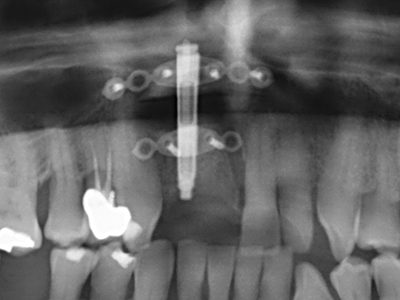

As shown in the past, basically any bone surgery procedure represents a possible indication for piezosurgery. Thus preparation of the mobile segment in distraction osteogenesis (Fig. 23-25) and sandwich osteotomy uses special attachments without endangering the blood supply to the crestal section, which is essential for the success of both techniques (Gonzalez-Garcia, Diniz-Freitas et al. 2008).